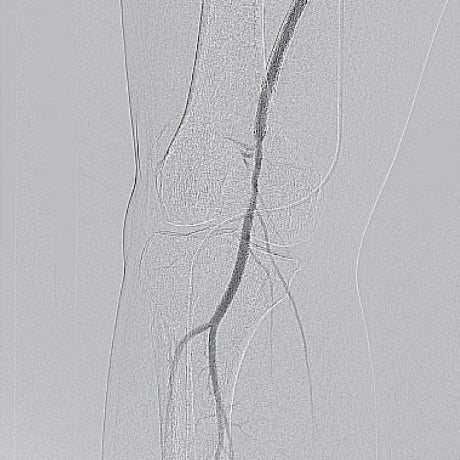

- ステント近位端のみではなく、遠位端やBMSとDESとの重複留置部の硬化が強く難渋したが、なんとか閉塞病変を通過(図3)